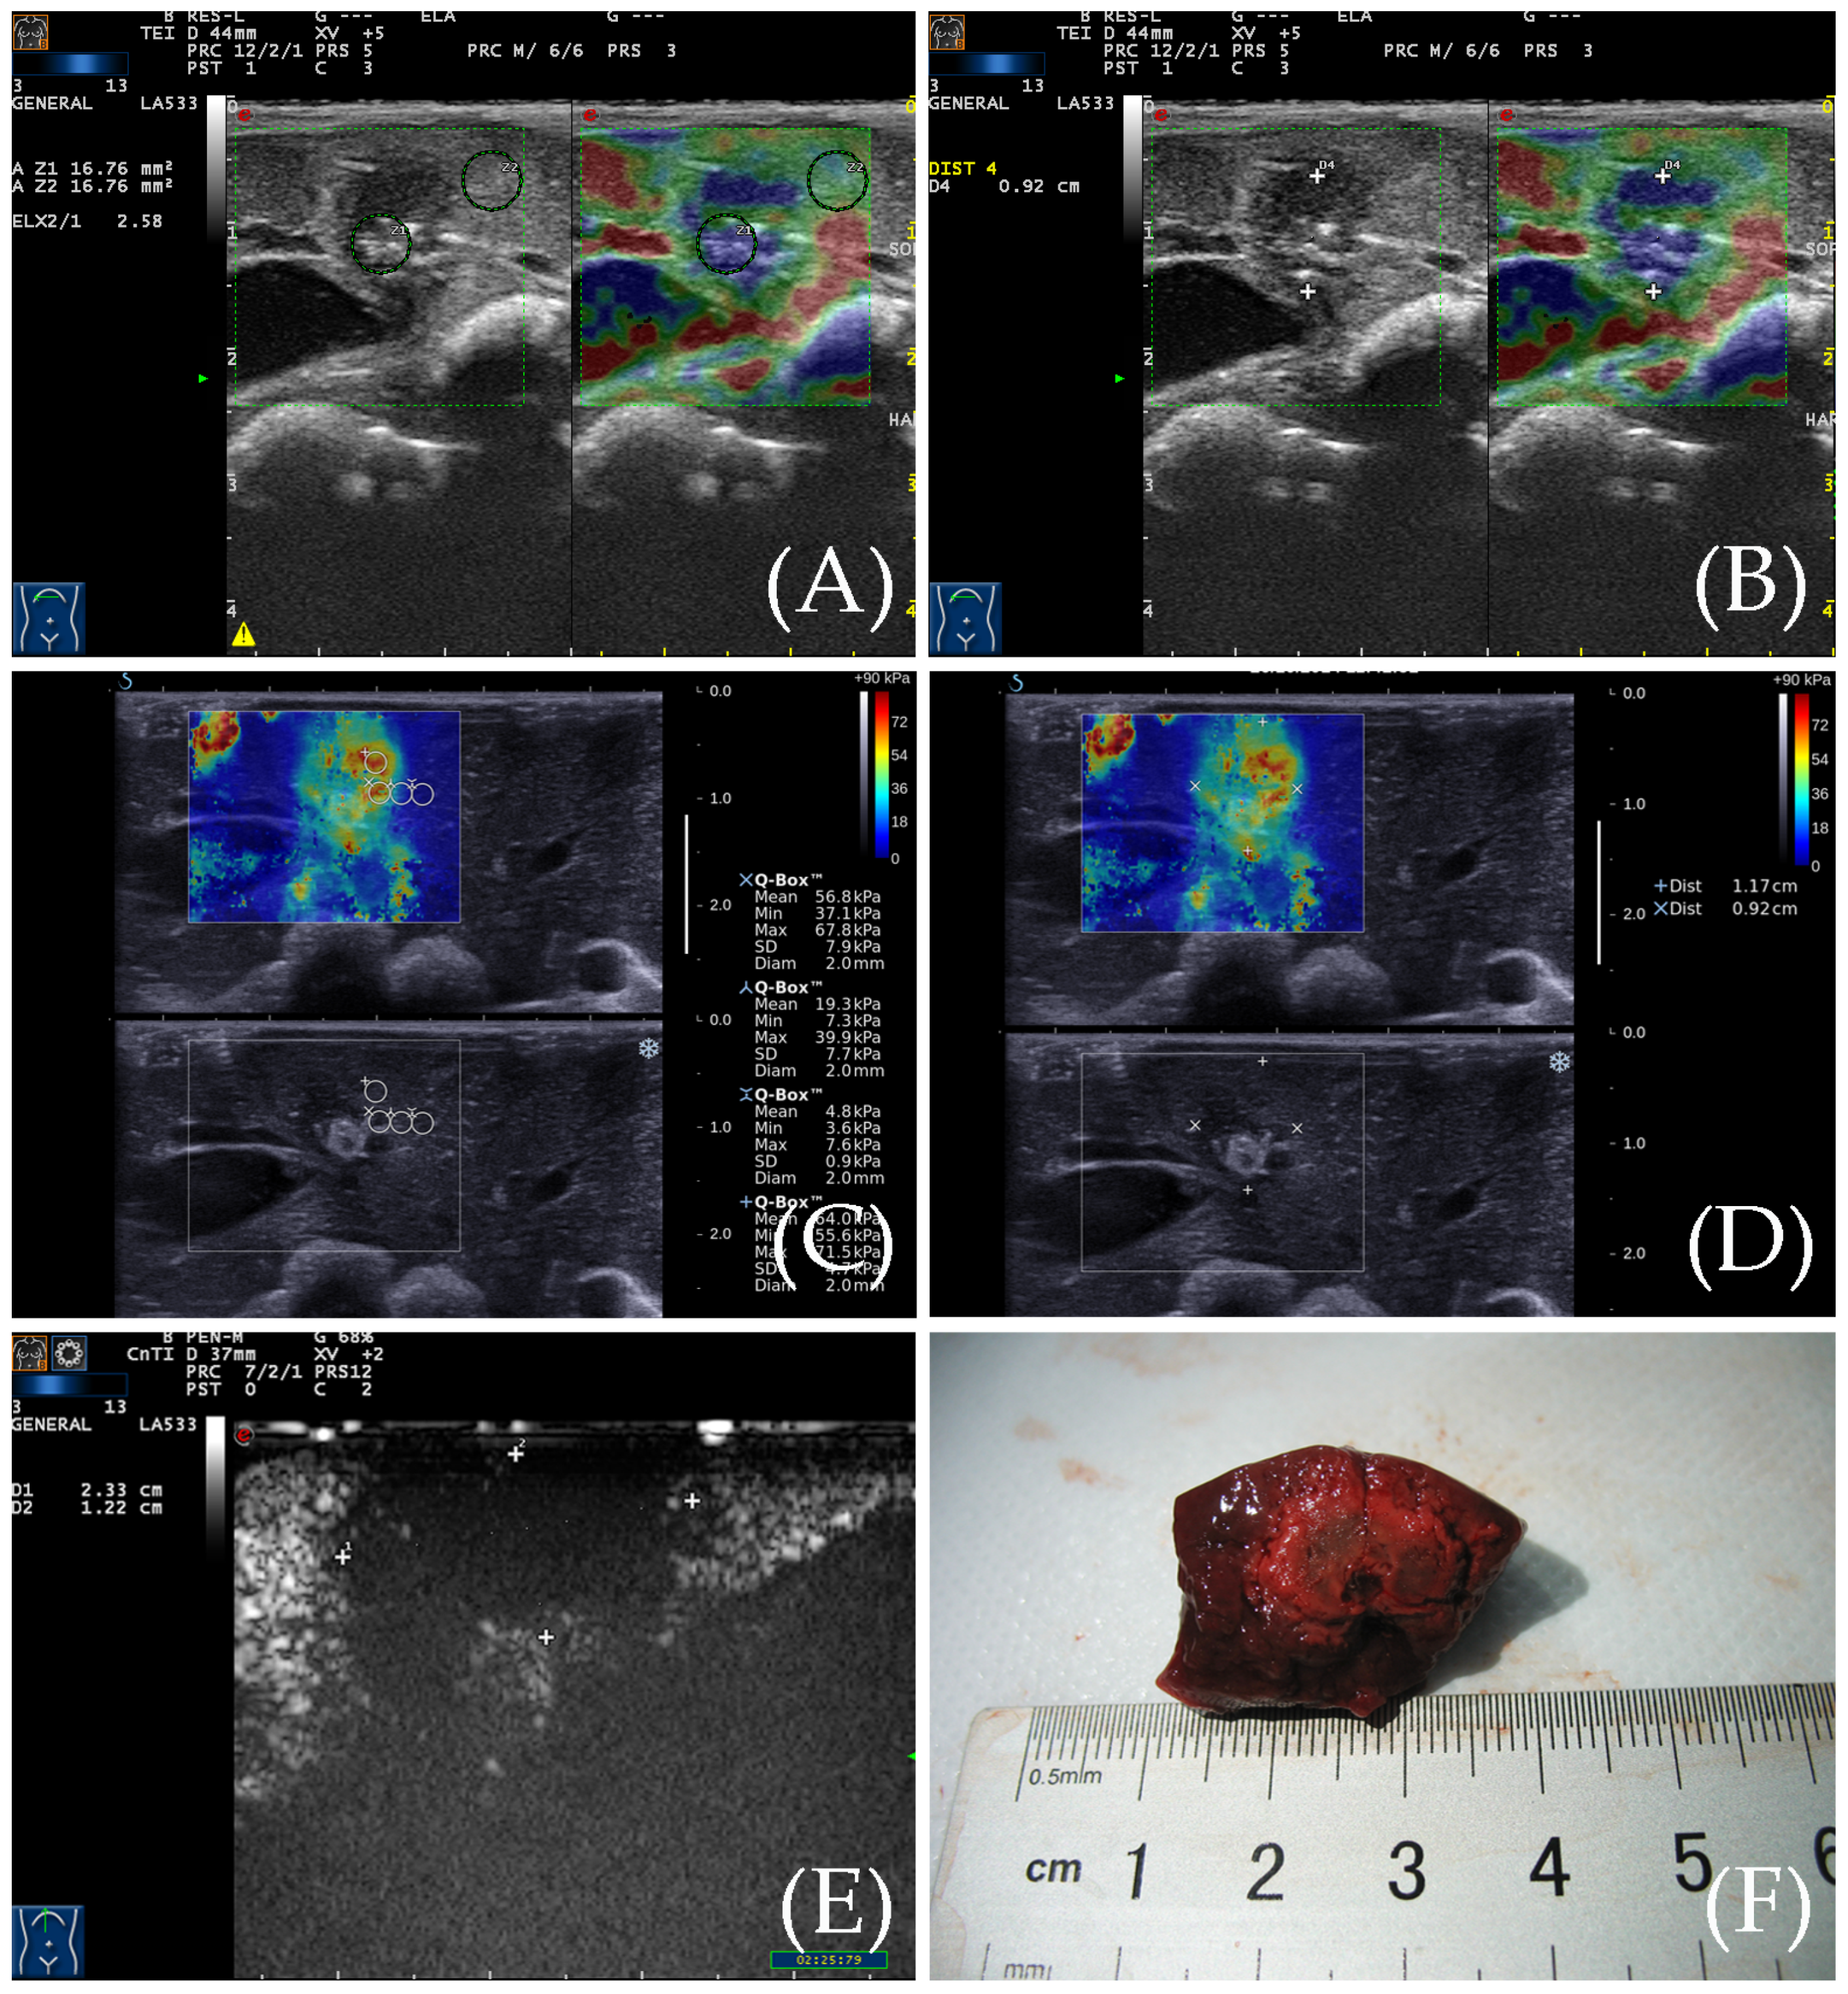

Figure 3. (A) RTE elasticity image of the ablation zone. The even blue indicates the ablation zone, and its boundary is clear. The yellow, green, and red indicate the peripheral normal liver. (B) The diameter of the ablation zone was measured according to the elasticity image. (C) SWE elasticity image of the ablation zone. The ablation zone is indicated by three colors: yellow, green, and red. The peripheral normal liver is indicated by an even blue color. (D) The diameter of the ablation zone was measured according to the elasticity image. (E) After CEUS, the diameter of the ablation zone was measured by CEUS image. (F) The gross specimen of the ablation zone was measured after sacrifice.

The RTE images showed that the ablation zone had a clear boundary, and was indicated by a homogeneous blue, while the surrounding normal liver tissue was indicated by yellow, green, and red colors (Figure 3). For RFA, the ratio of the elastic value of the ablation zone rim to the surrounding normal liver tissue was 3.41 ± 0.67 (2.23–4.76). The area of the ablation zone measured by RTE was 1.089 ± 0.199 cm2 for RFA.

3.3. SWE for the Detection of the Ablation Zone

From SWE, we can also see the ablation zone had a clear boundary. The ablation zone showed a yellow–green–red tricolor change, and the surrounding normal liver tissue showed a uniform blue color. A 2 mm sampling frame was used to measure the elasticity of the ablation zone from the center to the periphery, and the changes in Young’s modulus values were analyzed. The Young’s modulus gradually decreases from the center of the ablation zone to the periphery (Figure 3). The Young’s modulus within the RFA ablation zone ranged widely from 33.2 to 70.4 kPa (50.7 ± 11.3 kPa), while the Young’s modulus at the edge of the ablation zone ranged from 25.1 to 36.3 kPa (28.5 ± 3.13 kPa) which was relatively stable. The area of the ablation zone was 1.059 ± 0.201 cm2 for RFA based on elastic images.

3.4. Contrast-Enhanced Ultrasound Examination

After the elastic examination, a CEUS examination was performed for the ablation zones of New Zealand rabbits. It indicated no enhancement during the entire period (Figure 3). The surrounding normal liver tissue indicated uniform iso-enhancement performance. The average area of the ablation zone was 3.091 ± 0.591 cm2 for RFA.

3.5. Gross Specimen Observation and Comparison of the Three Imaging Methods